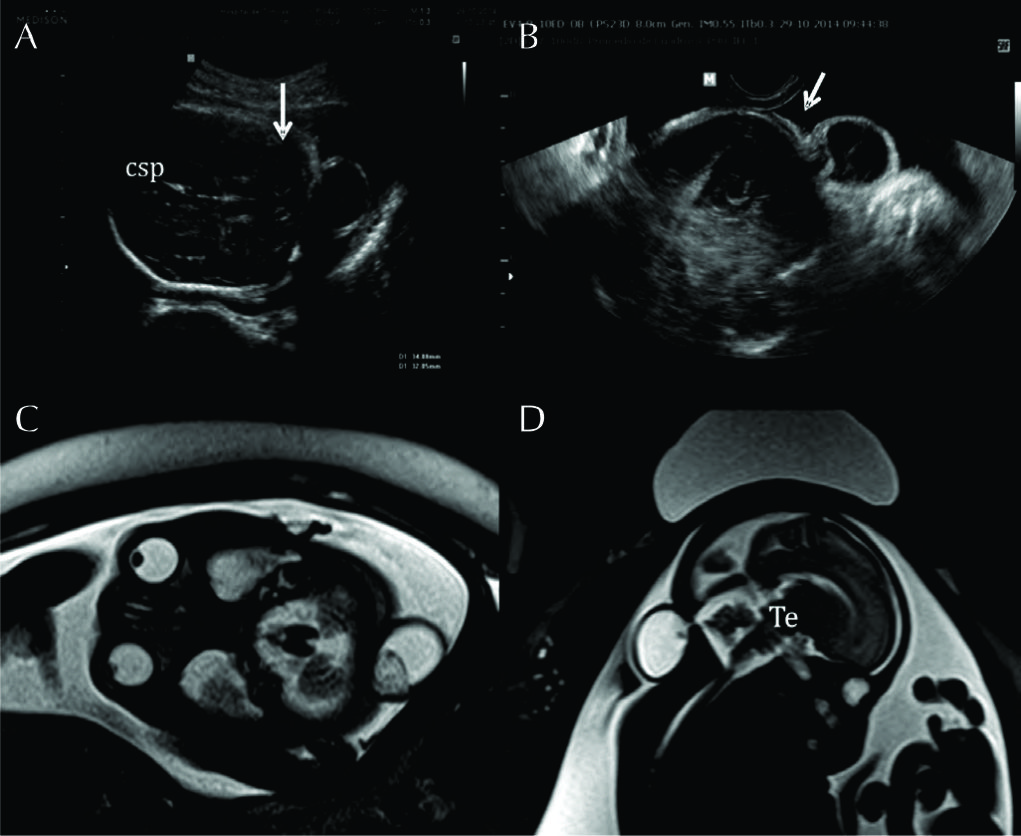

Figura 4

RM Fetal Hidrocefalia por Estenosis del acueducto.

Se presentan 2 casos de fetos con hidrocefalia (HCF) por estenosis del acueducto. El primer caso se presenta con HCF leve/moderada (A sagital y B axial) donde puede observarse la dilatación ventricular supra-tentorial con IV ventrículo normal lo que orienta al diagnóstico de estenosis del acueducto.

En C se muestra imagen sagital del 2º caso con HCF severa y ausencia de señal en el acueducto de Sylvio lo que orienta al diagnóstico (è). AV: Atrio ventricular

CC: cuerpo calloso

Te: Tronco encefálico

Ce: Cerebelo

Figura 5

RM Fetal Hidranencefalia.

RMf a las 29 semanas de edad gestacional en paciente referido para confirmación de hidranencefalia, diagnóstico diferencial de HCF extrema. En A imagen sagital donde se observa la dilatación del sistema ventricular con estructuras de la fosa posterior de anatomía normal al igual que el IV ventrículo.

En B imagen coronal donde se observa la severa dilatación de los ventrículos laterales y se observan ambos tálamos (T) de aspecto normal con 3er ventrículo entre ellos.

En los cortes axiales (C y D) se observan los elementos ya destacados y además se corrobora otra estructura de línea media como la hoz cerebral (HC) y la presencia de escaso manto cerebral a nivel occipital (MC). Esto permite diferenciar esta entidad de las prosencefalias. Te: Tronco encefálico Ce: Cerebelo